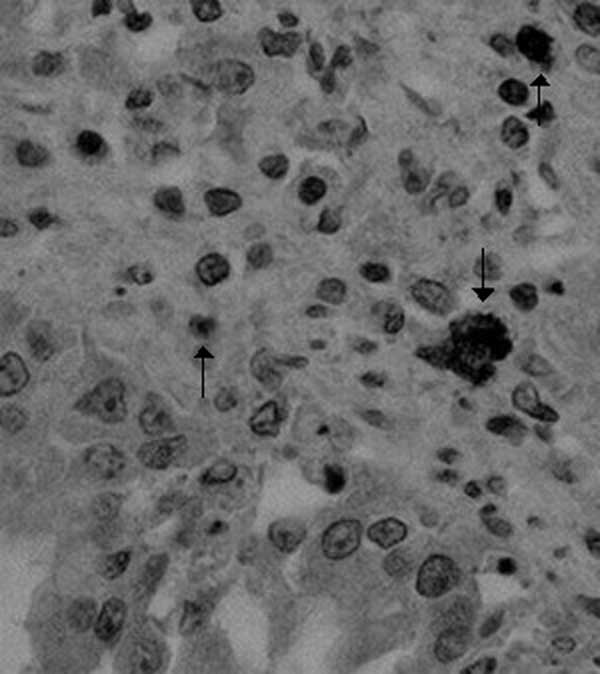

Realizarse una prueba de VIH es un paso fundamental para la detección temprana del virus de inmunodeficiencia humana y el acceso a tratamiento oportuno. Para garantizar resultados precisos, es esencial acudir a laboratorios o clínicas especializadas que cumplan con estándares de calidad y seguridad en el manejo de las muestras. Existen diversos métodos de diagnóstico, cada uno con una función específica en la detección del virus o la evaluación de la respuesta inmunitaria del organismo.

Existen diversos métodos de diagnóstico, cada uno con una función específica en la detección del virus o la evaluación de la respuesta inmunitaria del organismo.